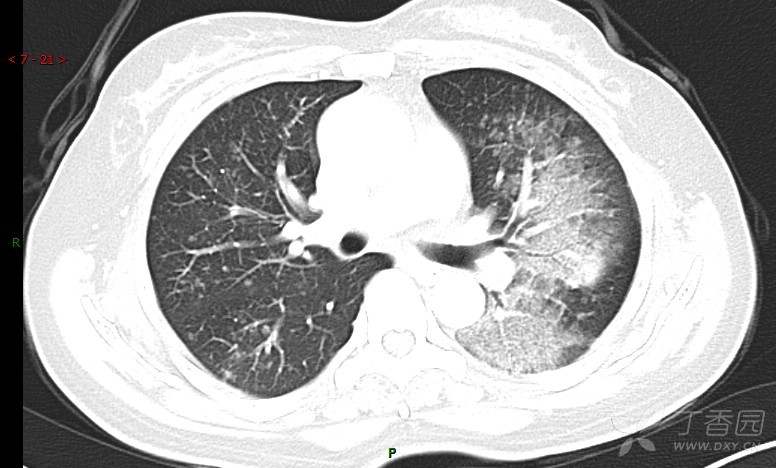

腺泡结节影,蜂窝征,这些都在提示……(病例3连发,附其他2例链接,病理已公布)

咳嗽1年余,加重7天。

患者于1年余前始受凉后出现咳嗽,多为干咳,未在意,未到医院就诊。近3月患者出现咳痰,多为黄色粘痰,量大,伴乏力,偶有头晕、心慌,无发热、胸痛、憋喘,无低热、盗汗、咯血、胸痛,无头痛,无恶心、呕吐、腹痛、腹泻,无尿频、尿急、尿痛,在当地诊所给予抗感染等对症支持治疗(具体药物及剂量不详),症状仍时有反复。患者于1月余前到外院就诊,行胸部CT提示双肺炎症,左肺重,考虑为“间质性肺炎”,给予“左氧氟沙星、利巴韦林、头孢哌酮舒巴坦钠注射液”治疗,复查胸部CT示病灶吸收不理想,后出院继续于诊所对症治疗(具体药物及剂量不详),效果欠佳。7天前患者无明显诱因出现上述症状加重,为求进一步诊治,特来我院就诊,我院门诊以“肺炎(重症)?”收入留观室,留观室给予“盐酸莫西沙星氯化钠”等对症治疗后,今日转入我科。患者自发病以来,神志清,精神差,饮食正常,睡眠增多,大小便正常,体重近3月减轻5公斤余。